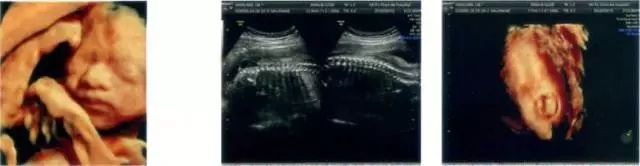

▲无脑儿,缺少头盖骨,脑髓暴露,不可能存活。

▲多指、少指,影响肢体正常功能,且不美观。